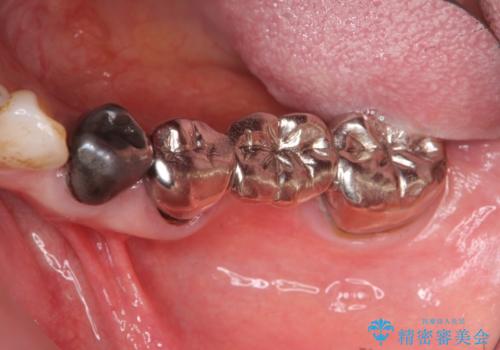

- 古くなり黒ずんできたブリッジのやりかえを希望され来院されました。

老朽化した銀パラジウム合金のブリッジを除去し、ジルコニア製のブリッジでやりかえを計画します。